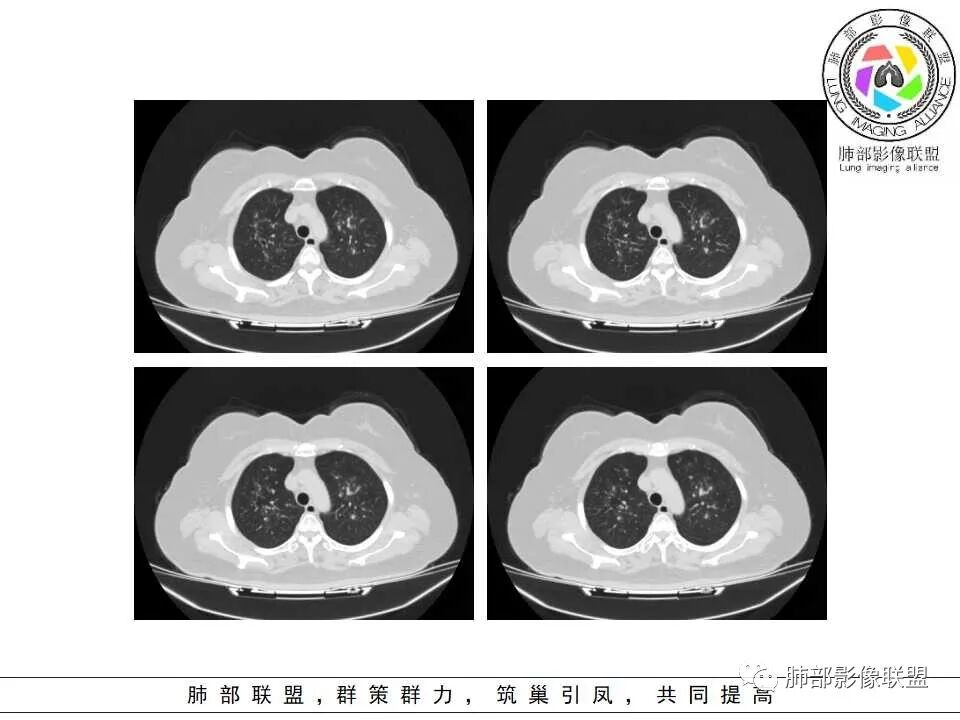

支气管壁增厚、毛糙,考虑气道侵袭性曲霉。

病史+支气管壁增厚+支气管肺炎影像病理基础的苏联红色革命+气喘=气道侵袭性曲霉

弥漫性支气管壁增厚,结合气管镜及痰鸣音,考虑气道曲霉

慢性病程,双肺支气管管壁增厚,周围可见多发点片状高密度影,边缘模糊不清,考虑气道侵袭性曲霉菌病

两肺支气管管壁增厚,沿支气管斑点状及斑片状高密度影,边缘模糊,考虑气道侵袭性曲霉菌,鉴别金葡萄、铜绿

居住地长年潮湿,老年女性,两肺支气管管壁增厚明显,考虑气道侵袭性曲霉菌,鉴别结核。

沿支气管血管束走形,气道壁增厚,边缘模糊,考虑考虑气道侵袭性曲霉,鉴别淋巴瘤。

中老年女性,气道分布的病变,有树芽树雾征,有支气管粘液栓,还有支气管壁增厚,考虑感染性病变,ABBA可能性大,鉴别支原体及军团,支原体以小孩多见,症状轻影像重,发病年龄及影像都不符合,患者住一楼,开麻将馆有聚集性,场地潮湿,不能排除军团肺炎!综合考虑ABBA,不排除军团

1.病灶沿支气管分布的特点相当明显,相应支气管壁广泛增厚。这种与支气管关系极为密切的片影和/或结节影,常高度提示气道相关感染,如支气管肺炎。

3.支气管壁广泛增厚对气道侵袭性曲霉病具有一定的提示意义。注意患者没有支气管扩张,临床也未提供IGE等实验室资料。

一,气道侵袭性曲霉病(PNTA)

1.器官支气管管套样壁增厚和/或支气管扩张,注意壁增厚较均匀,和/或伴有播散性小片影及结节影,注意这些小片影或结节影边界有时较普通炎性病灶清楚。